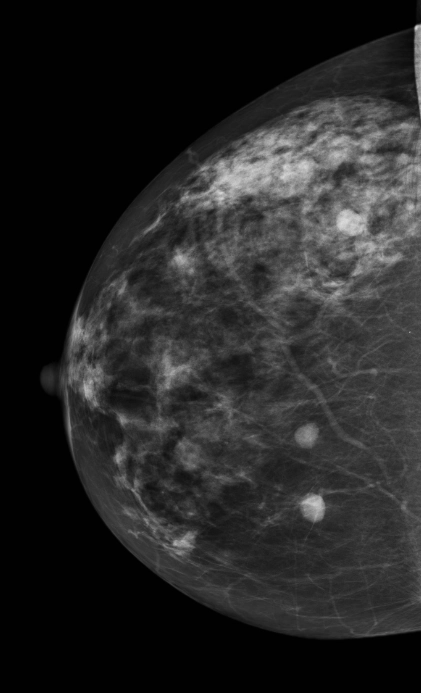

U ác tính

Ung thư biểu mô tiểu thùy xâm nhập của tuyến vú (Invasive lobular carcinoma of the breast)